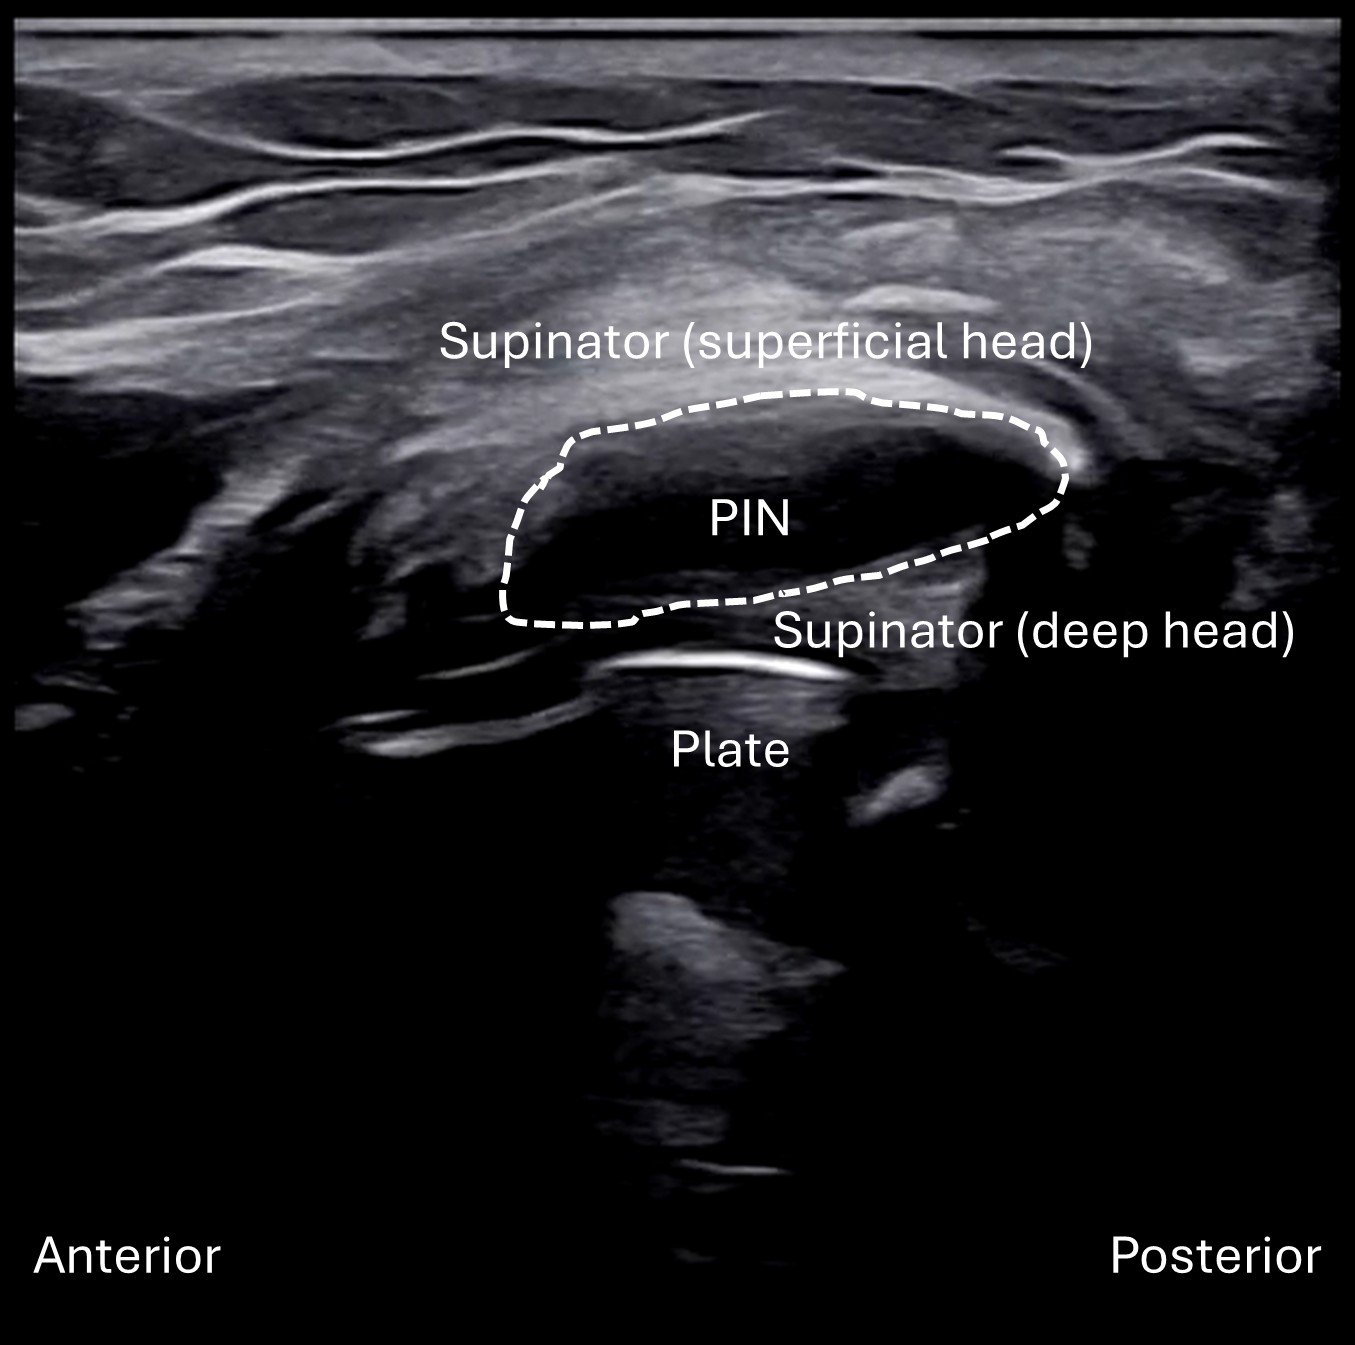

Labeled short axis view of the left PIN within the radial tunnel. In this view, the PIN (dashed oval) becomes focally hypoechoic and enlarged (25.75 mm2). It is seen situated between hyperechoic superficial and deep heads of the supinator muscle, likely secondary to muscle denervation. As seen in the above view, the PIN sits superficial to the underlying radius plate from the prior ORIF for the proximal radius fracture.

Unlabeled short axis view of the left PIN within the radial tunnel.